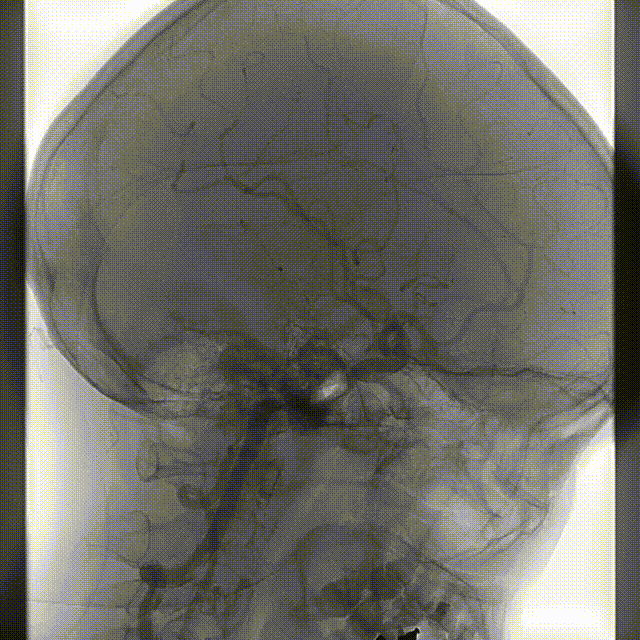

术中DSA造影:右侧颈内动脉3D造影提示:右侧颈内动脉床突旁大型动脉瘤,大小约为20.72×16.33mm,远端血管直径1.92mm,近端血管直径3.48mm。

完全释放FRED 4017血流导向密网支架辅助弹簧圈栓塞后,正、侧位及3D造影观察,载瘤动脉通畅、支架贴壁良好、动脉瘤内造影剂滞留。